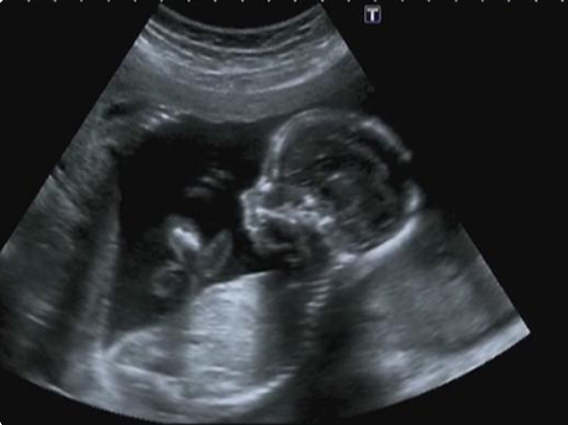

怀孕40天双胎b超图片和单胎b超单对比后有什么区别?

怀孕40天双胎和单胎b超单对比后的区别就在于孕囊个数不同,还有可见的胎心、胎芽数量都不一样。虽然早孕期胎儿还没有形成一定的形状,但是这个时候是可以通过B超图像来观察到是双胎还是单胎的,若是在宫腔内可以明显看到两个妊娠囊,两个卵黄囊,两个胎芽和两个胎心,就可以直接判断该孕妇是双胎妊娠。在确定怀孕之后,高兴之余千万不要忘记定期去做产检,即便是早孕期胎儿还没有开始发育,定期的产检也是不能懈怠的,而且一